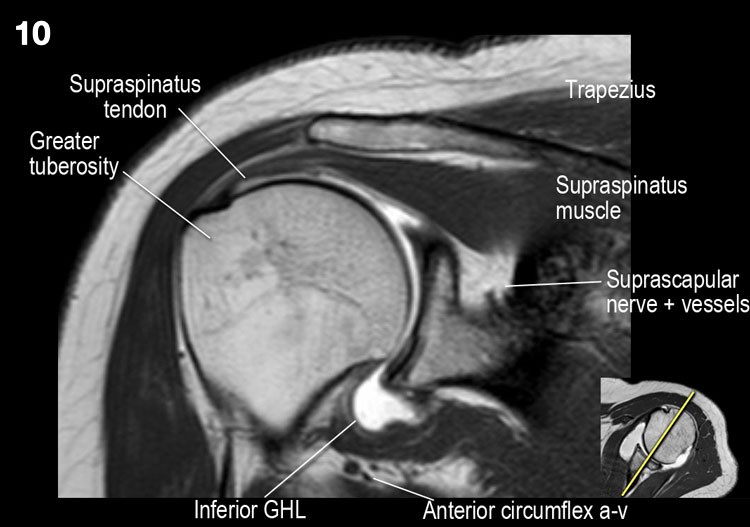

Giải phẫu mặt cắt vành và danh sách kiểm tra

- Lưu ý dây chằng quạ-mỏm cùng vai.

- Lưu ý thần kinh và mạch máu trên vai.

- Tìm kiếm hội chứng chèn ép cơ trên gai do gai xương khớp cùng-đòn hoặc dây chằng quạ-mỏm cùng vai dày lên.

- Tìm kiếm tràn dịch quá mức trong túi hoạt dịch dưới mỏm cùng vai và rách gân cơ trên gai.

- Tìm kiếm rách kiểu “rim-rent” của gân cơ trên gai tại chỗ bám của các thớ sợi trước.

- Đánh giá chỗ bám của dây chằng ổ chảo-cánh tay dưới (IGHL) vào xương cánh tay. Đánh giá phức hợp sụn viền-dây chằng phần dưới. Tìm kiếm tổn thương HAGL (bong điểm bám dây chằng ổ chảo-cánh tay tại xương cánh tay).

- Tìm kiếm rách gân cơ dưới gai.

- Lưu ý tổn thương Hill-Sachs nhỏ.

- Tìm kiếm rách gân cơ trên gai.